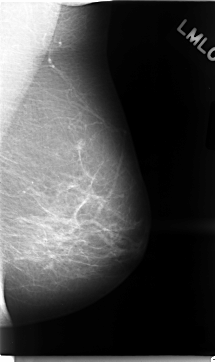

C_0022_1.LEFT_MLO

LEFT_MLO LINES 4696 PIXELS_PER_LINE 2792 BITS_PER_PIXEL 12 RESOLUTION 50 NON_OVERLAY